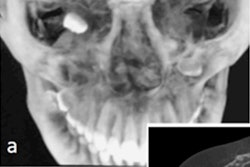

Diagnostic radiography (a) before and (b) after removal of the metal ceramic crown. All images courtesy of Mothanna AlRahabi, PhD, and Hani Ghabbani, BDS. Licensed under CC BY-NC 4.0.The man had undergone a root canal retreatment at a general dental practice before he was referred. He was diagnosed with apical periodontitis, which critically influences the outcome of root canal treatment. Therefore, removing the separated instrument was necessary to improve the prognosis of the root canal, according to the authors.

X-rays showed that the separated instrument extended along the root canal to the apical foramen of the canine, which had a metal ceramic crown. After the crown was isolated, another x-ray was taken and showed another small separated instrument in the pulp chamber, they wrote.